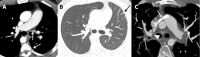

Congenital pulmonary artery anomalies represent a diverse group of abnormalities, ranging from asymptomatic incidental findings to causes of sudden cardiac death. While some may be recognized in childhood, others may be found incidentally in adulthood. We review the clinical and imaging findings in patients with congenital anomalies of the pulmonary arteries, including valvular and perivavular anomalies as well as abnormal narrowing, course and communications of the pulmonary arteries. We also discuss the role of various imaging modalities in the evaluation of these patients. It is vital to be aware of the key radiologic manifestations and associated haemodynamic consequences in these conditions in order to facilitate accurate diagnosis and prognostic stratification.